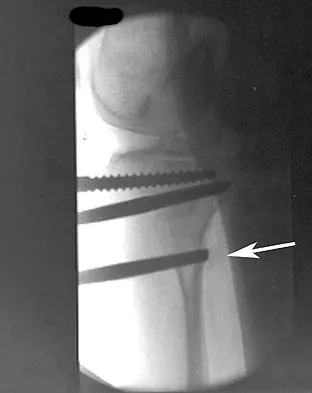

A 78-year-old patient undergoing revision total knee arthroplasty has bone loss throughout the knee at the time of revision. A distal femoral augment is used to restore the joint line. One month after surgery, the patient reports pain and is unable to ambulate. A lateral radiograph is shown in Figure 34. What is the most likely etiology of this problem?

Explanation